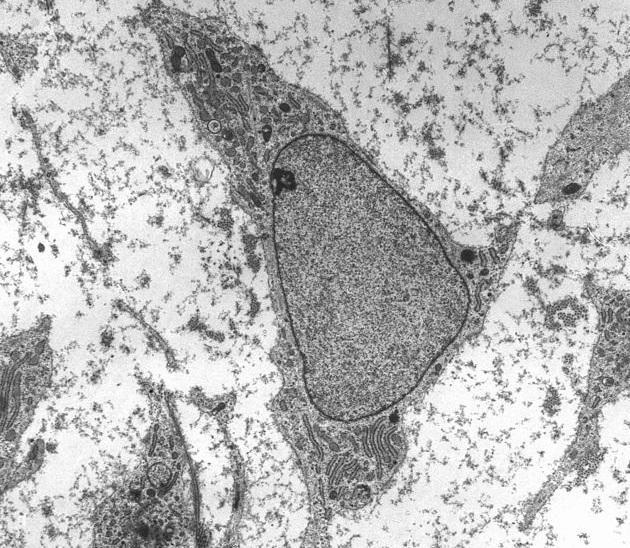

• Células madre: Estas células tienen la capacidad de diferenciarse en diferentes tipos de tejidos, lo que las convierte en una herramienta prometedora para reparar lesiones óseas, cartilaginosas y tendinosas.

• Factores de crecimiento: Son proteínas que estimulan la proliferación y diferenciación celular, acelerando la reparación de tejidos dañados.